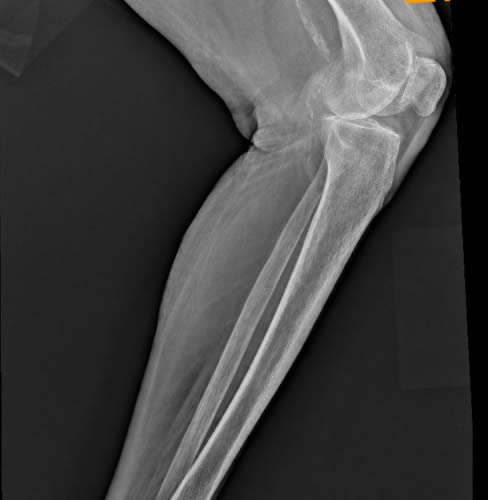

Οι ακτινογραφίες πραγματοποιούνται με πλήρως ψηφιακό εξοπλισμό και όχι ψηφιοποιημενο από έμπειρους Τεχνολόγους – Ακτινολόγους με άδεια ασκήσεως Επαγγέλματος.

Ο πιο σύγχρονος φορητός Ακτινολογικός εξοπλισμός πλήρως ψηφιακής απεικόνισης (DR) σε μια κινητή ακτινολογική μονάδα, μπορεί να επισκεφθεί τον ασθενή οπουδήποτε στην περιοχή της Θεσσαλονίκης και των περιχώρων και να σταλεί, αν ο ασθενής το επιθυμεί, η γνωματευμένη ακτινογραφία ηλεκτρονικά μέσω διαδικτύου στον θεράποντα- παραπέμποντα ιατρό ο οποίος θα λάβει το αποτέλεσμα στο προσωπικό του υπολογιστή, tablet, Smartphone οπουδήποτε κι αν βρίσκεται.

Άμεση παράδοση της ακτινογραφίας και της γνωμάτευσης λίγα λεπτά μετά την άφιξη της ακτινολογικής μονάδας. Δυνατότητα επανάληψης της ακτινογραφίας για την παραγωγή του βέλτιστου αποτελέσματος, εξαιτίας της ψηφιακής αυτόματης εμφάνισης της ακτινογραφίας που γίνεται στην οικία του ασθενούς